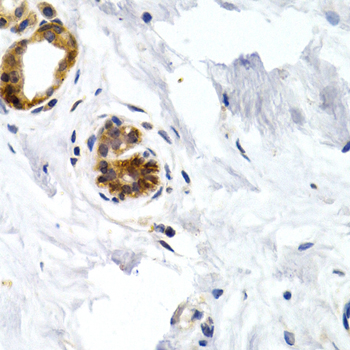

Immunohistochemistry of paraffin-embedded human normal breast using GDF5 antibody at dilution of 1:200 (400x lens).